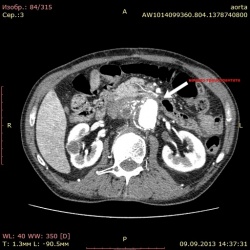

Пациент 28 лет, КТ выполнялась "на почки". Параллельно нашел такие изменения. Коллеги, правильно ли я их трактую как апофиз(или последствие травмы?) и мягкая бляшка брюшной аорты? БЛЯШКА....

21.10.2013 - 09:28